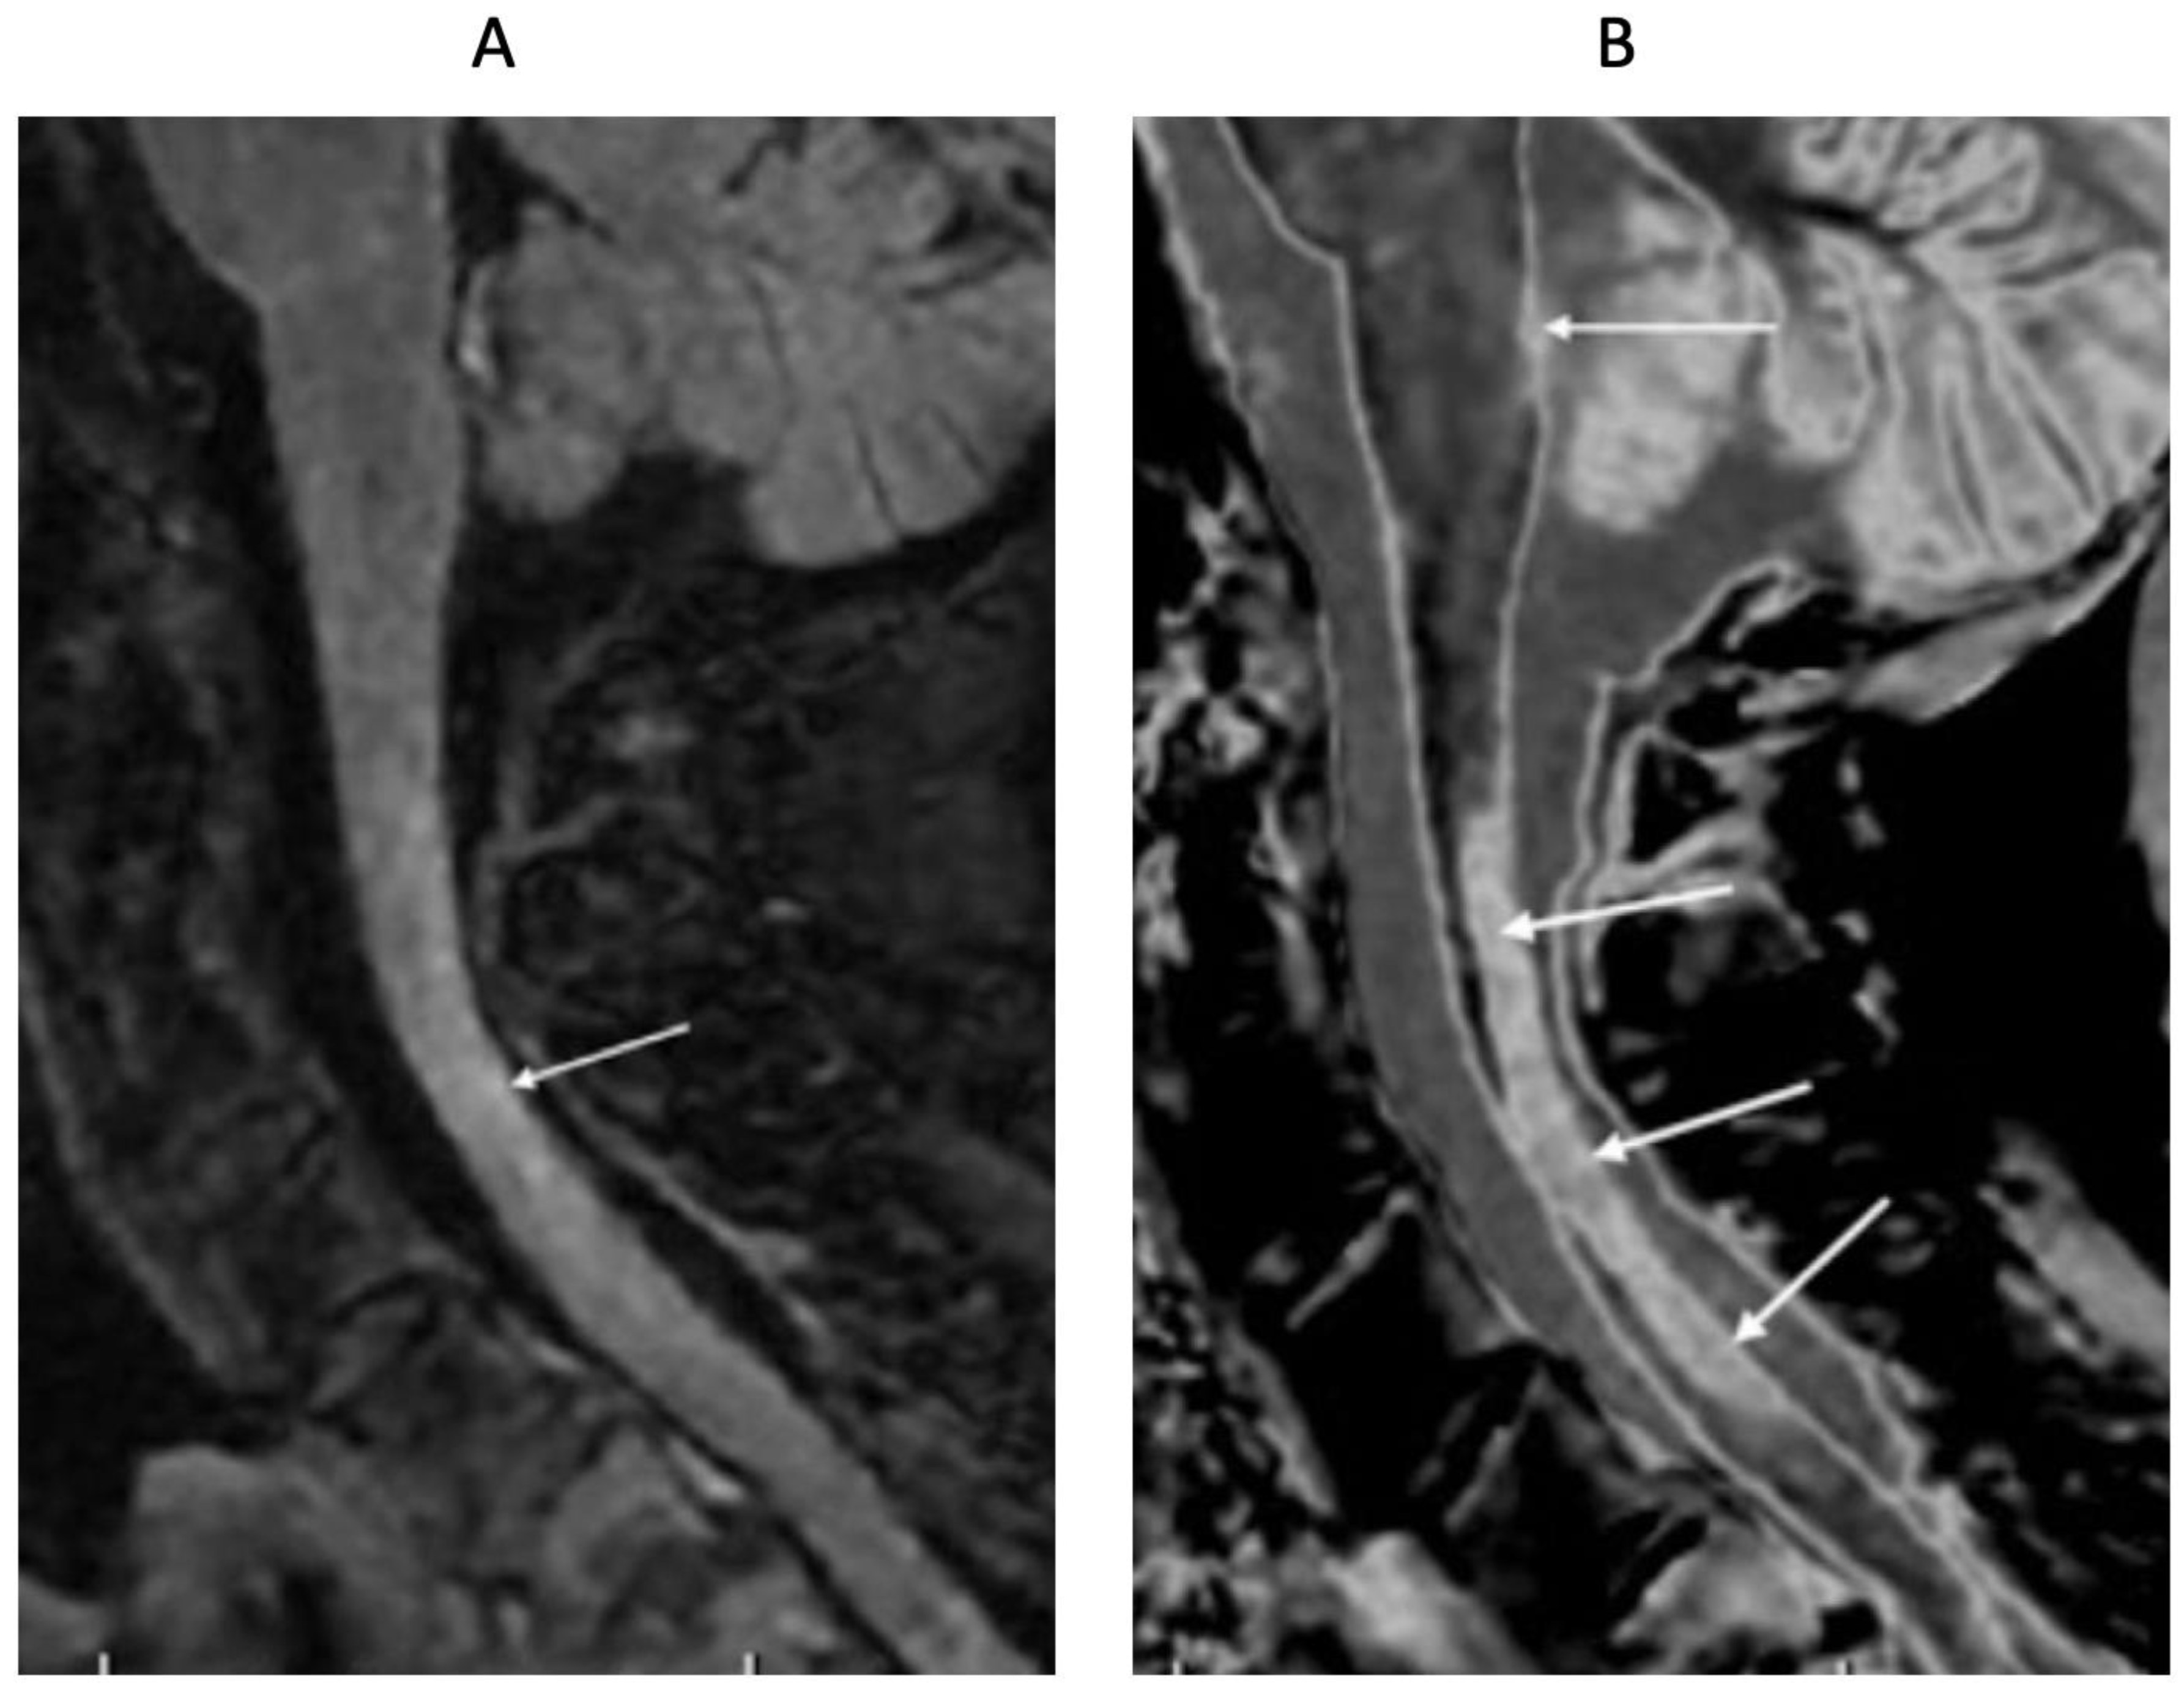

In the spinal cord in another patient diagnosed with MS, the T

2-FLAIR image only shows an ill-defined smudge (arrow) (

Figure 18A). The corresponding wide mD dSIR image (

Figure 18B) shows an extensive, well defined, high contrast abnormality (arrows). Another lesion is seen in the medulla on the dSIR image (arrow) but not on the T

2-FLAIR image.

76-year-old female patient in remission with a diagnosis of MS. Sagittal 3D T2-FLAIR (A) and 3D wide mD dSIR (T1-BLAIR) (B) images. The T2-FLAIR image shows a poorly defined area of increased signal in the cervical cord (arrow). The T1-BLAIR image shows a high contrast lesion with sharply defined (“punched out”) boundaries in the cervical cord (lower three arrows). This is much more extensive than in (A). An additional lesion is seen in the medulla on the T1-BLAIR image in the region of the area postrema (highest arrow) (B) but not on the T2-FLAIR image (A). The extended lesion in the cervical cord and the lesion in the area postrema raise the possibility of neuromyelitis optica spectrum disorder. Other conventional sequences such as T2-wSE or STIR may perform better than T2-FLAIR in the cervical cord.

Figure 18.